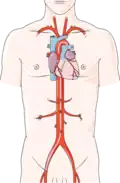

Perkutánní transluminální angioplastika (PTA) (perkutánní = vpichem přes kůži), zkráceně angioplastika, je chirurgický zákrok intervenční radiologie, při kterém je do postiženého místa zúžené cévy zaveden katétr, jenž má za cíl zvětšit průřez cévy, případně odstranit nebo porušit blokující aterosklerotické pláty. V závislosti na funkci katétru rozlišujeme balónkovou angioplastiku (cévy jsou roztahovány tlakem přes 100 metrů vodního sloupce, tj cca MPa) nebo laserovou angioplastiku. Obvykle je v místě zákroku implantován stent zamezující opětovnému zúžení cévy. Naprostá většina zákroků se provádí na srdečních tepnách při řešení hrozícího, nebo probíhajícího infarktu myokardu.

Perkutánní koronární intervence (PCI), dříve označovaná jako angioplastika koronárních cév (PCTA) obvykle přímo navazuje na koronarografické vyšetření.[1][2][3] Katétr je zaveden vpichem do tepny v třísle nebo na zápěstí. Na rozdíl od jiných katetrizací srdce, perkutánní koronární intervence cíleně vstupuje do jednotlivých věnčitých tepen.

Po převozu na katetrizační sál („katlab“) vstupuje kardiolog tepnou do krevního oběhu

Po převozu na katetrizační sál („katlab“) vstupuje kardiolog tepnou do krevního oběhu -